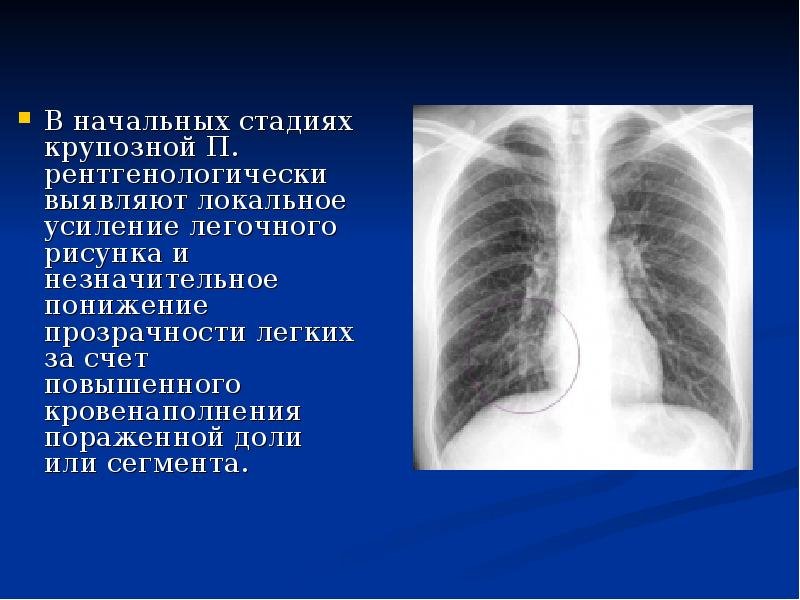

Усиление сосудистого рисунка легких на рентгене - это явление, которое может быть наблюдаемо при проведении рентгенологического исследования органов дыхания. В результате усиления сосудистого рисунка, на снимке становятся более заметными сосуды, расположенные внутри легких. Это может свидетельствовать о различных патологических процессах, таких как воспаление легких, обструкция дыхательных путей или сердечная недостаточность. Усиление сосудистого рисунка является важным признаком для постановки диагноза и выбора оптимального лечения. Однако, для точной интерпретации рентгеновского снимка необходимо учитывать и другие клинические данные, а также провести дополнительные исследования, если необходимо.